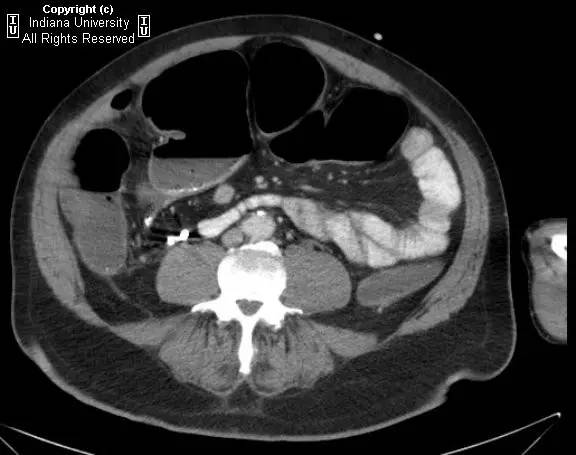

【影像学表现】右侧腹部可见曲线样不透亮区,1周后位置有变化(似进入盲肠)。横结肠显著扩张、充气。CT上扩张原因不明,无明确的梗阻证据。

【诊断】阑尾内对比剂充填